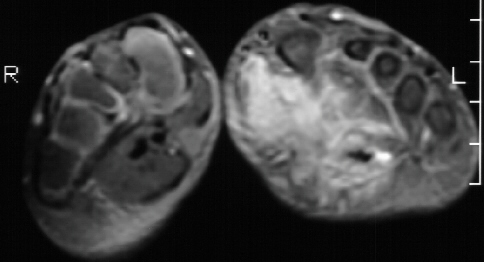

A 6 year old female presented to Outpatient Clinic with mass in her

left foot which the mother says has been getting bigger and causes pain

when the child walks for more than a few steps. There was firm tender mass

within the planter arch area of the left foot. the mass was approximately

6.5 x l7 cm. It involved virtually the entire arch of the foot. An xray

embolisation of left foot arteriovenous malformation. The current MRI is

above.

MRI is the most specific study to define the borders of a hemangioma for

which surgical excision is planned.